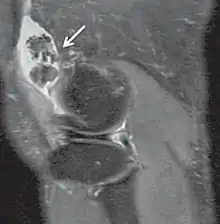

| Proton density weighted | PD | Long TR (to reduce T1) and short TE (to minimize T2).[7] | Joint disease and injury.[8]

Proton density (PD)- weighted images are created by having a long repetition time (TR) and a short echo time (TE).[36] On images of the brain, this sequence has a more pronounced distinction between grey matter (bright) and white matter (darker grey), but with little contrast between brain and CSF.[36] It is very useful for the detection of arthropathy and injury.[37]